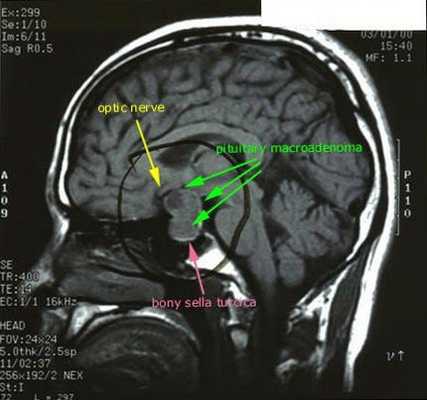

Синдром Иценко-Кушинга – это сочетание клинических симптомов, вызванных хроническим повышением уровня кортизола или родственных ему кортикостероидов в крови. Болезнь Иценко-Кушинга – это синдром Кушинга, причиной которого служит избыточная гипофизарная продукция адренокортикотропного гормона (АКТГ), как правило, обусловленная небольшой доброкачественной опухолью гипофиза – аденомой. Иногда АКТГ производится опухолью, которая не связана с гипофизом, она может находиться где угодно, чаще - в легких и грудной клетке. Порой злокачественные опухоли хорошо маскируются под железы и начинают вырабатывать гормоны альдостерон и кортизол, что, в свою очередь, приводит к повышению их концентраций в человеческом организме. При этом собственные железы понемногу начинают атрофироваться - таким образом организм старается бороться с избытком гормонов.

Основная причина заболевания — кортикотрофная микроаденома (доброкачественная опухоль) гипофиза. Возникновение последней может быть связано со множеством факторов. Часто заболевание развивается после травмы головного мозга, беременности, родов, нейроинфекции.

При БИК в 80-85% случаев выявляют микроаденому гипофиза (опухоль до 10 мм), у остальных 15-20% — макроаденому (доброкачественное новообразование от 10 мм). [7]